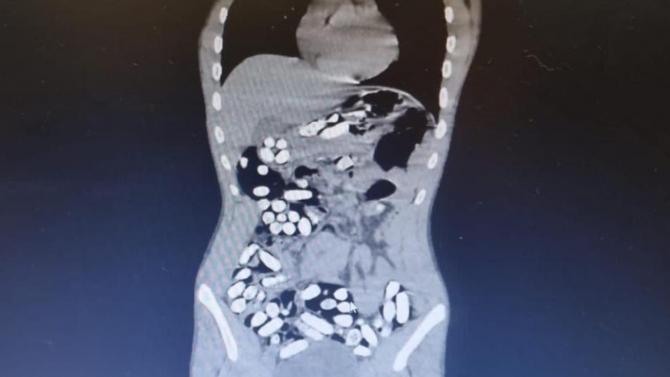

Çekilen röntgen filmlerinde şüphelilerin vücutlarında 62 kapsül eroin ve 210 kapsül afyon sakızı olduğu tespit edildi.

İç organlarının her tarafına yayıldığı belirlendi

Röntgen çekimlerinde uyuşturucu kapsüllerinin şüphelilerin neredeyse iç organlarının her tarafına yayıldığı belirlendi.

Doktor ve polis, vücutta tek seferde bu kadar yüklü miktarda uyuşturucu görmenin şaşkınlığını yaşadı.